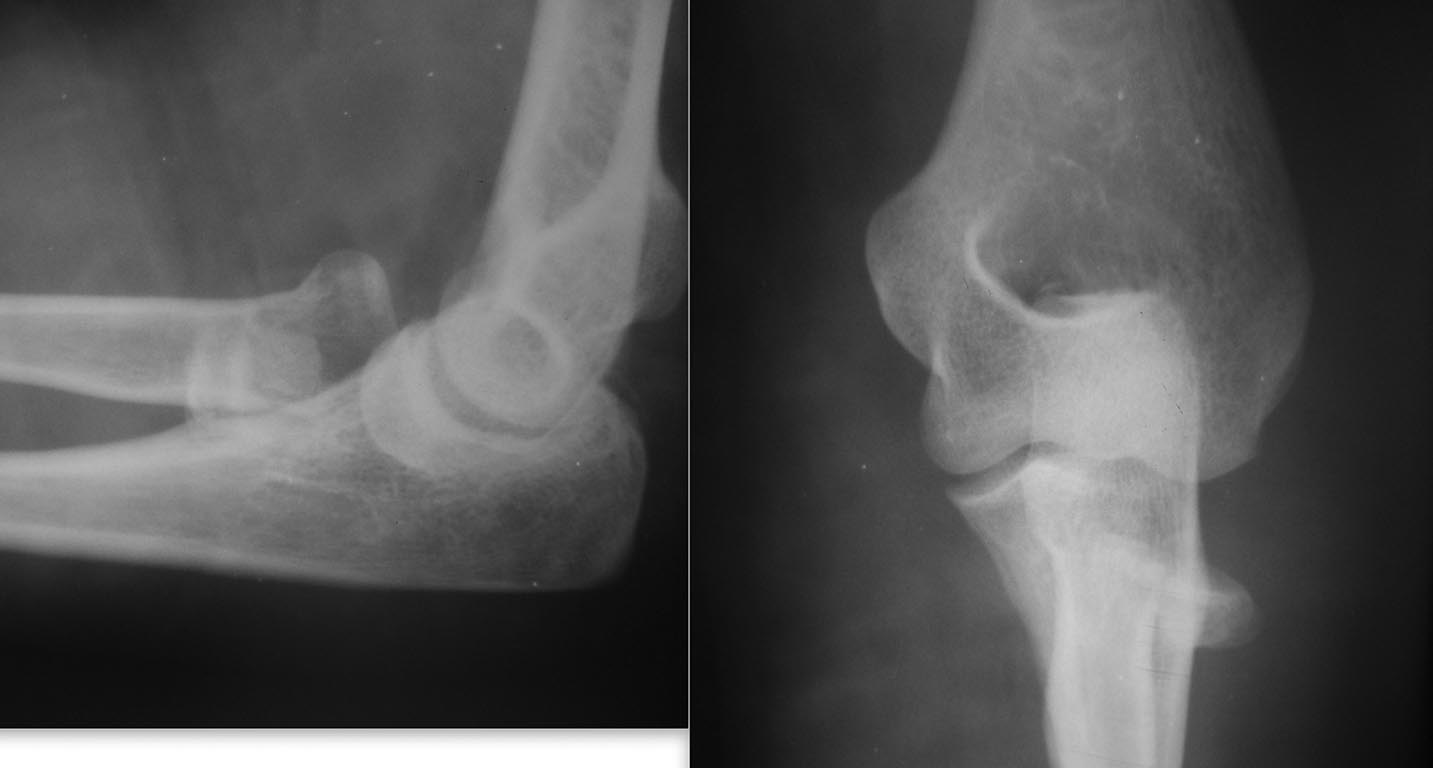

Перелом головки лучевой кости

Доброго времени суток, коллеги! Обратилась молодая женщина. Травма в быту 8 дней назад.

Доброго времени суток, коллеги! Обратилась молодая женщина. Травма в быту 8 дней назад. Хотелось узнать мнение сообщества по лечению данных повреждений. Синтезировать или удалять, если удаление, то на каком уровне? Заранее благодарю.